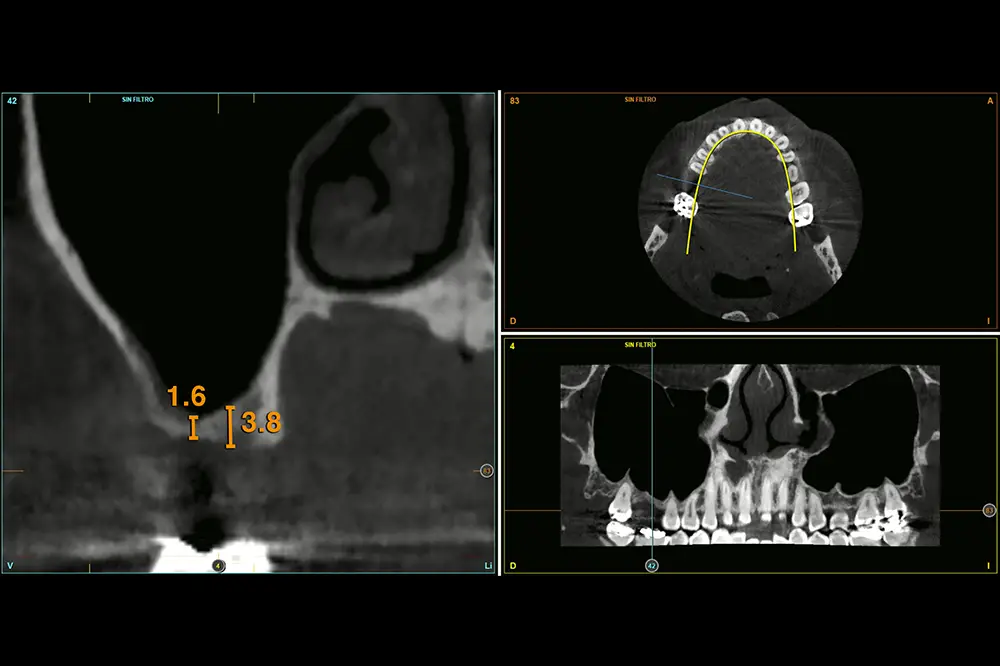

En este caso, la paciente acude con la exodoncia realizada hace dos años de la pieza 16 y una gran atrofia vertical, existiendo únicamente 1 mm en algunas zonas de la cresta, como el área más vestibular, y hasta 3 en la zona más palatina (fig. 9). Procedemos a la realización del fresado tal como se ha descrito en el caso anterior y colocamos el mismo tipo de injerto (autólogo y PRGF- Endoret) y un implante de 4,5 mm de longitud (fig. 10 y 11). Tras la cicatrización a los 4 meses, observamos el aspecto de la zona de la colocación del implante, donde tenemos ahora una altura de 7 mm (fig. 12).

Fig. 9. Cone-beam de planificación donde observamos la escasa altura residual de la cresta a nivel de la pieza 16.

Fig. 12. Estado de la zona una vez consolidado el injerto a los 4 meses.